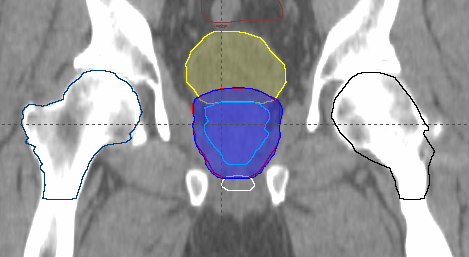

Planning Activities

Prostate Case – Contouring

Prostate Case – Planning